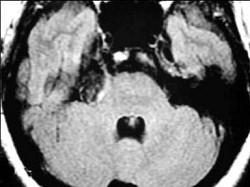

男,42岁,右侧听力下降,MRI检查如图,最可能的诊断为()A.表皮样囊肿B.听神经瘤C.三叉神经瘤D.脑膜瘤E.脑梗死

问题 男,42岁,右侧听力下降,MRI检查如图,最可能的诊断为()

选项 A.表皮样囊肿 B.听神经瘤 C.三叉神经瘤 D.脑膜瘤 E.脑梗死

答案 A